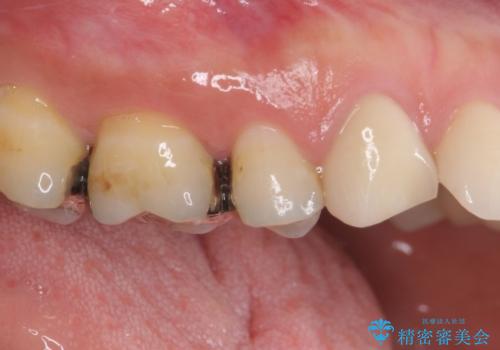

- 奥歯に痛みを感じるようになり、更にはその前の歯のセラミックが欠けてしまったとのことで来院された患者様です。

痛みがしばらく続いていたため、抜髄となる可能性を考慮しながら処置を行うこととしました。

処置後に痛みの状態を確認し、前歯のクラウンの再製作を同時に進めることとしました。

銀歯の下の虫歯はそれほど大きくなく、初回の処置以降、痛みを感じることはなくなりました。

セラミックインレー装着後も痛みが生じることはなく、神経の状態も正常な反応が認められました。